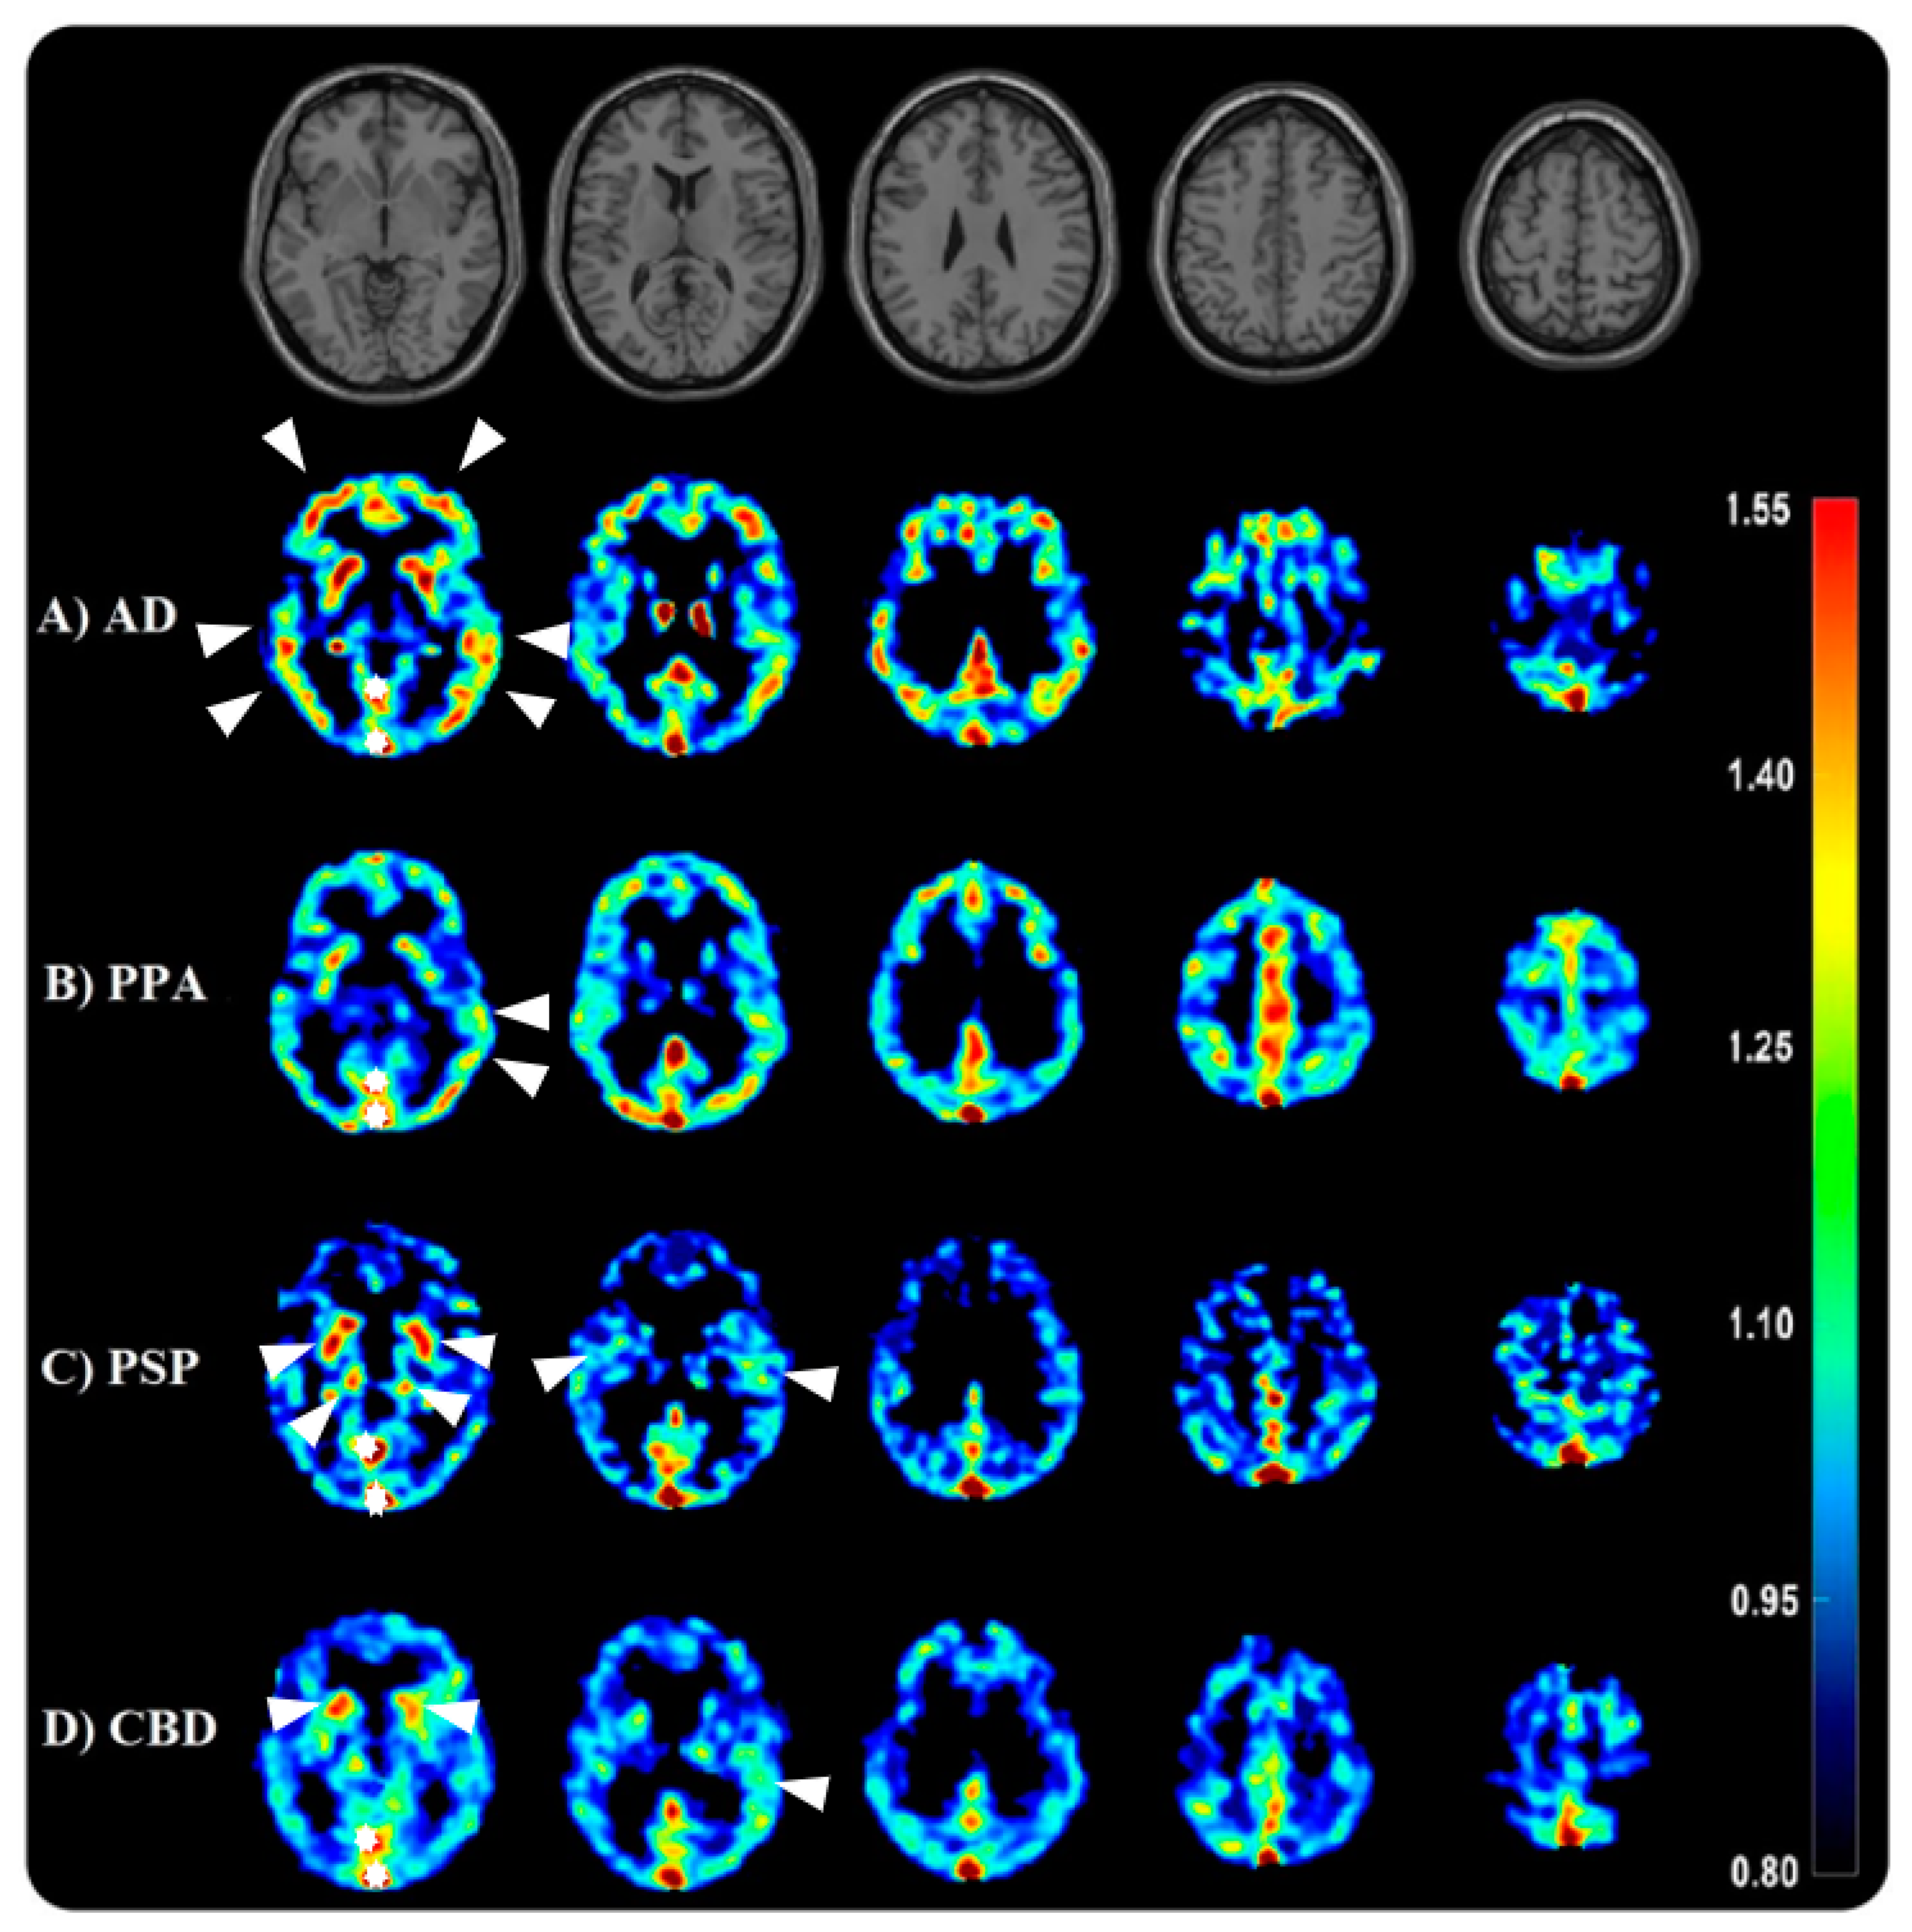

- Passamonti, L.; Vázquez Rodríguez, P.; Hong, Y.T.; Allinson, K.S.J.; Williamson, D.; Borchert, R.J.; Sami, S.; Cope, T.E.; Bevan-Jones, W.R.; Jones, P.S.; et al. 18F-AV-1451 positron emission tomography in Alzheimer’s disease and progressive supranuclear palsy. Brain A J. Neurol. 2017, 140, 781–791. [Google Scholar] [CrossRef]